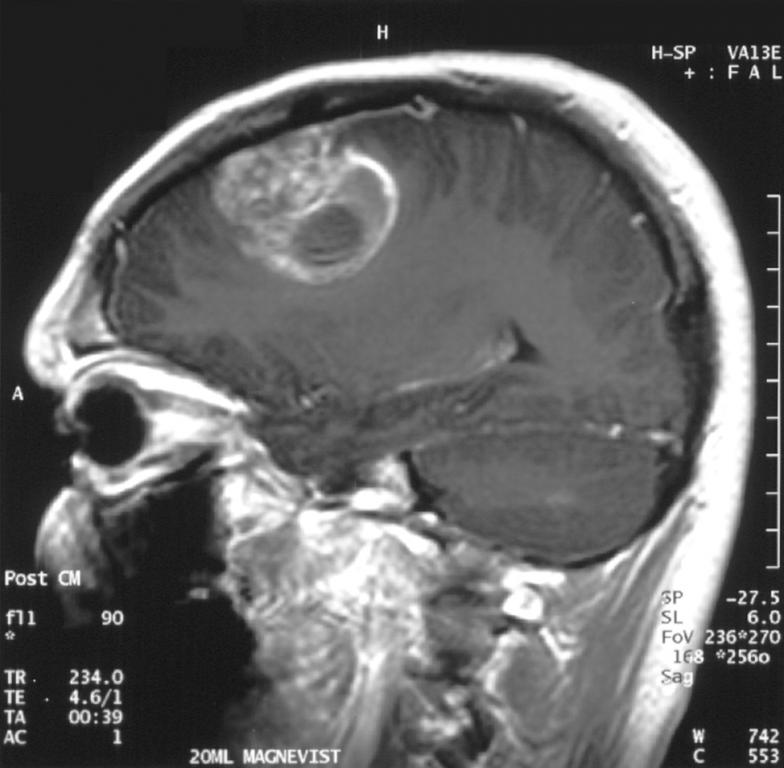

Болезнь нужно предотвращать, а не лечить — это девиз современной диагностической медицины и в частности «Клиники № 1». Медицинский центр специализируется на МРТ (магнитно-резонансная томография). Это точный метод, который исключает субъективное мнение врача. Как уверяют специалисты «Клиники № 1», МРТ — это один из самых безопасных, но максимально информативных методов диагностики состояния внутренних органов.

Томографию можно проходить столько раз, сколько нужно, поскольку нет рентгеновского облучения. Ничего ещё медицина не придумала лучше МРТ для диагностики работы головного или спинного мозга. Боитесь инсульта, есть предрасположенность к онкозаболеваниям — проверьте себя сейчас, чтобы была возможность предотвратить серьёзное заболевание. Поверьте, что диагностика менее затратна по деньгам и времени, чем продолжительное мучительное лечение.

В «Клинике № 1» отличный МРТ-аппарат, мощностью 1.5 Тесла. Врачи клиники проводят более 80 видов обследований: головного мозга и сосудов, всех отделов позвоночника, суставов и мягких тканей, молочных желез, внутренних органов и органов малого таза, программа онкопоиска. Описание проводится в режиме онлайн врачами г. Москвы с многолетним стажем и опытом работы на МРТ. Заключение выдается в течение 30 мин. после обследования. Девиз медицинского центра: «Точный диагноз — правильное лечение»!